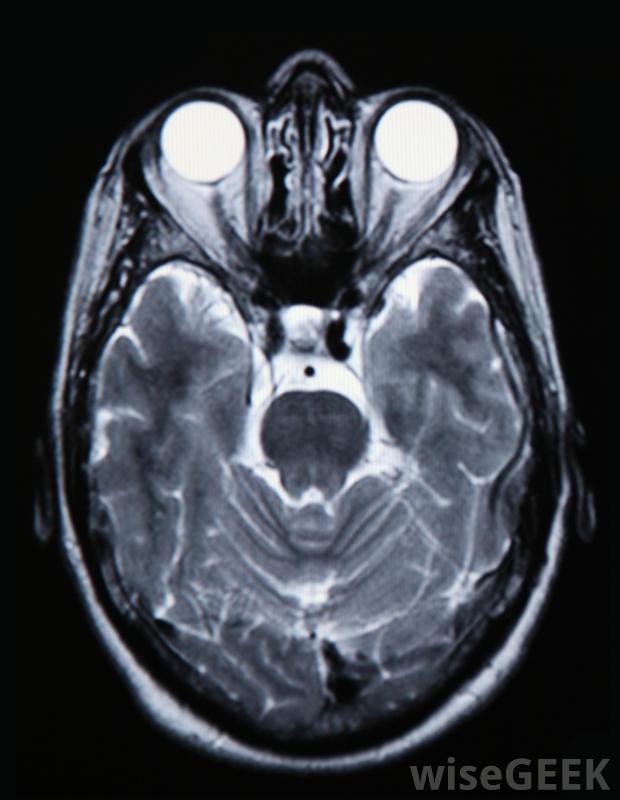

腦部瘀傷的癥狀是什么(Signs of Brain Bruising)?

腦挫傷的常見癥狀還與其他頭部損傷有關,如腦震蕩。這些癥狀包括頭部受到撞擊后失去意識、頭暈、易怒、嘔吐和說話含糊不清。患者在執行包括行走在內的多項運動技能時可能會出現問題。此外,一只眼睛的瞳孔可能比另一只眼睛大,患者可能會出現癲癇發作或身體一側肢體活動受限。眼睛周圍的瘀傷可能是腦部瘀傷的跡象腦挫傷的跡象會提醒個人,包括那些接近病人的人,頭部受到嚴重撞擊可能導致嚴重的身體狀況。一個人可能會有腦震蕩和瘀傷,因為這兩種情況都是由于大腦撞擊到患者的顱骨內部造成的,所以確定一個人患有腦挫傷的唯一方法就是把他送到醫院或其他醫療機構腦部掃描將向醫生顯示是否存在腦挫傷。有些癥狀更為特定于腦挫傷,而不是由頭部的撞擊。由于對大腦的撞擊,這個人的眼睛或耳朵周圍可能會有瘀傷另外,從病人鼻子、嘴或耳朵流出的透明液體表明大腦的蓋子已經破裂,伴隨著腦挫傷,液體從頭部流出。兒童,尤其是那些不能說話的孩子,可能是孩子腦部挫傷后經常出現的腦部挫傷,也可能是孩子腦部受創后出現的一種不同程度的瘀傷,也可能是由于孩子的腦部不斷受挫傷而引起的也不要對通常能吸引他的注意力的玩具或其他他平時喜歡的活動感興趣。如果一個人在頭部受到重擊后出現上述癥狀,他需要立即就醫。通常情況下,病人會被密切觀察,直到醫生能掃描出是否有腦挫傷。醫生也可以要求做血液檢查,它可以揭示患者大腦任何潛在損傷的重要細節。除非由合格的醫學專業人士進行治療,否則腦挫傷可能是致命的。沒有醫療干預,不可能明確地說出一個人的大腦是否有瘀傷。